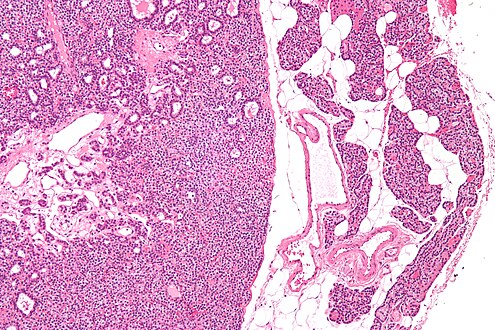

Parathyroid Adenoma

A parathyroid adenoma is a benign tumor of the parathyroid gland. It generally causes hyperparathyroidism; there are very few reports of parathyroid adenomas that were not associated with hyperparathyroidism.[1]

Before surgery is attempted, the affected glandular tissue must be located. Though the parathyroid glands are usually located on the back of the thyroid, their position is variable. Some people have one or more parathyroid glands elsewhere in the neck anatomy or in the chest. About 10% of parathyroid adenomas are ectopic, located not along the back of the thyroid but elsewhere in the body, sometimes in the mediastinum of the chest.[9] This can make them difficult to locate, so various imaging techniques are used, such as the sestamibi scan, single-photon emission computed tomography (SPECT), ultrasound, MRI,[9] and CT scans.[9][11] sometimes parathyroid adenomas can be ablated by ethanol injection, laser or radiofrequency guided by ultrasound.